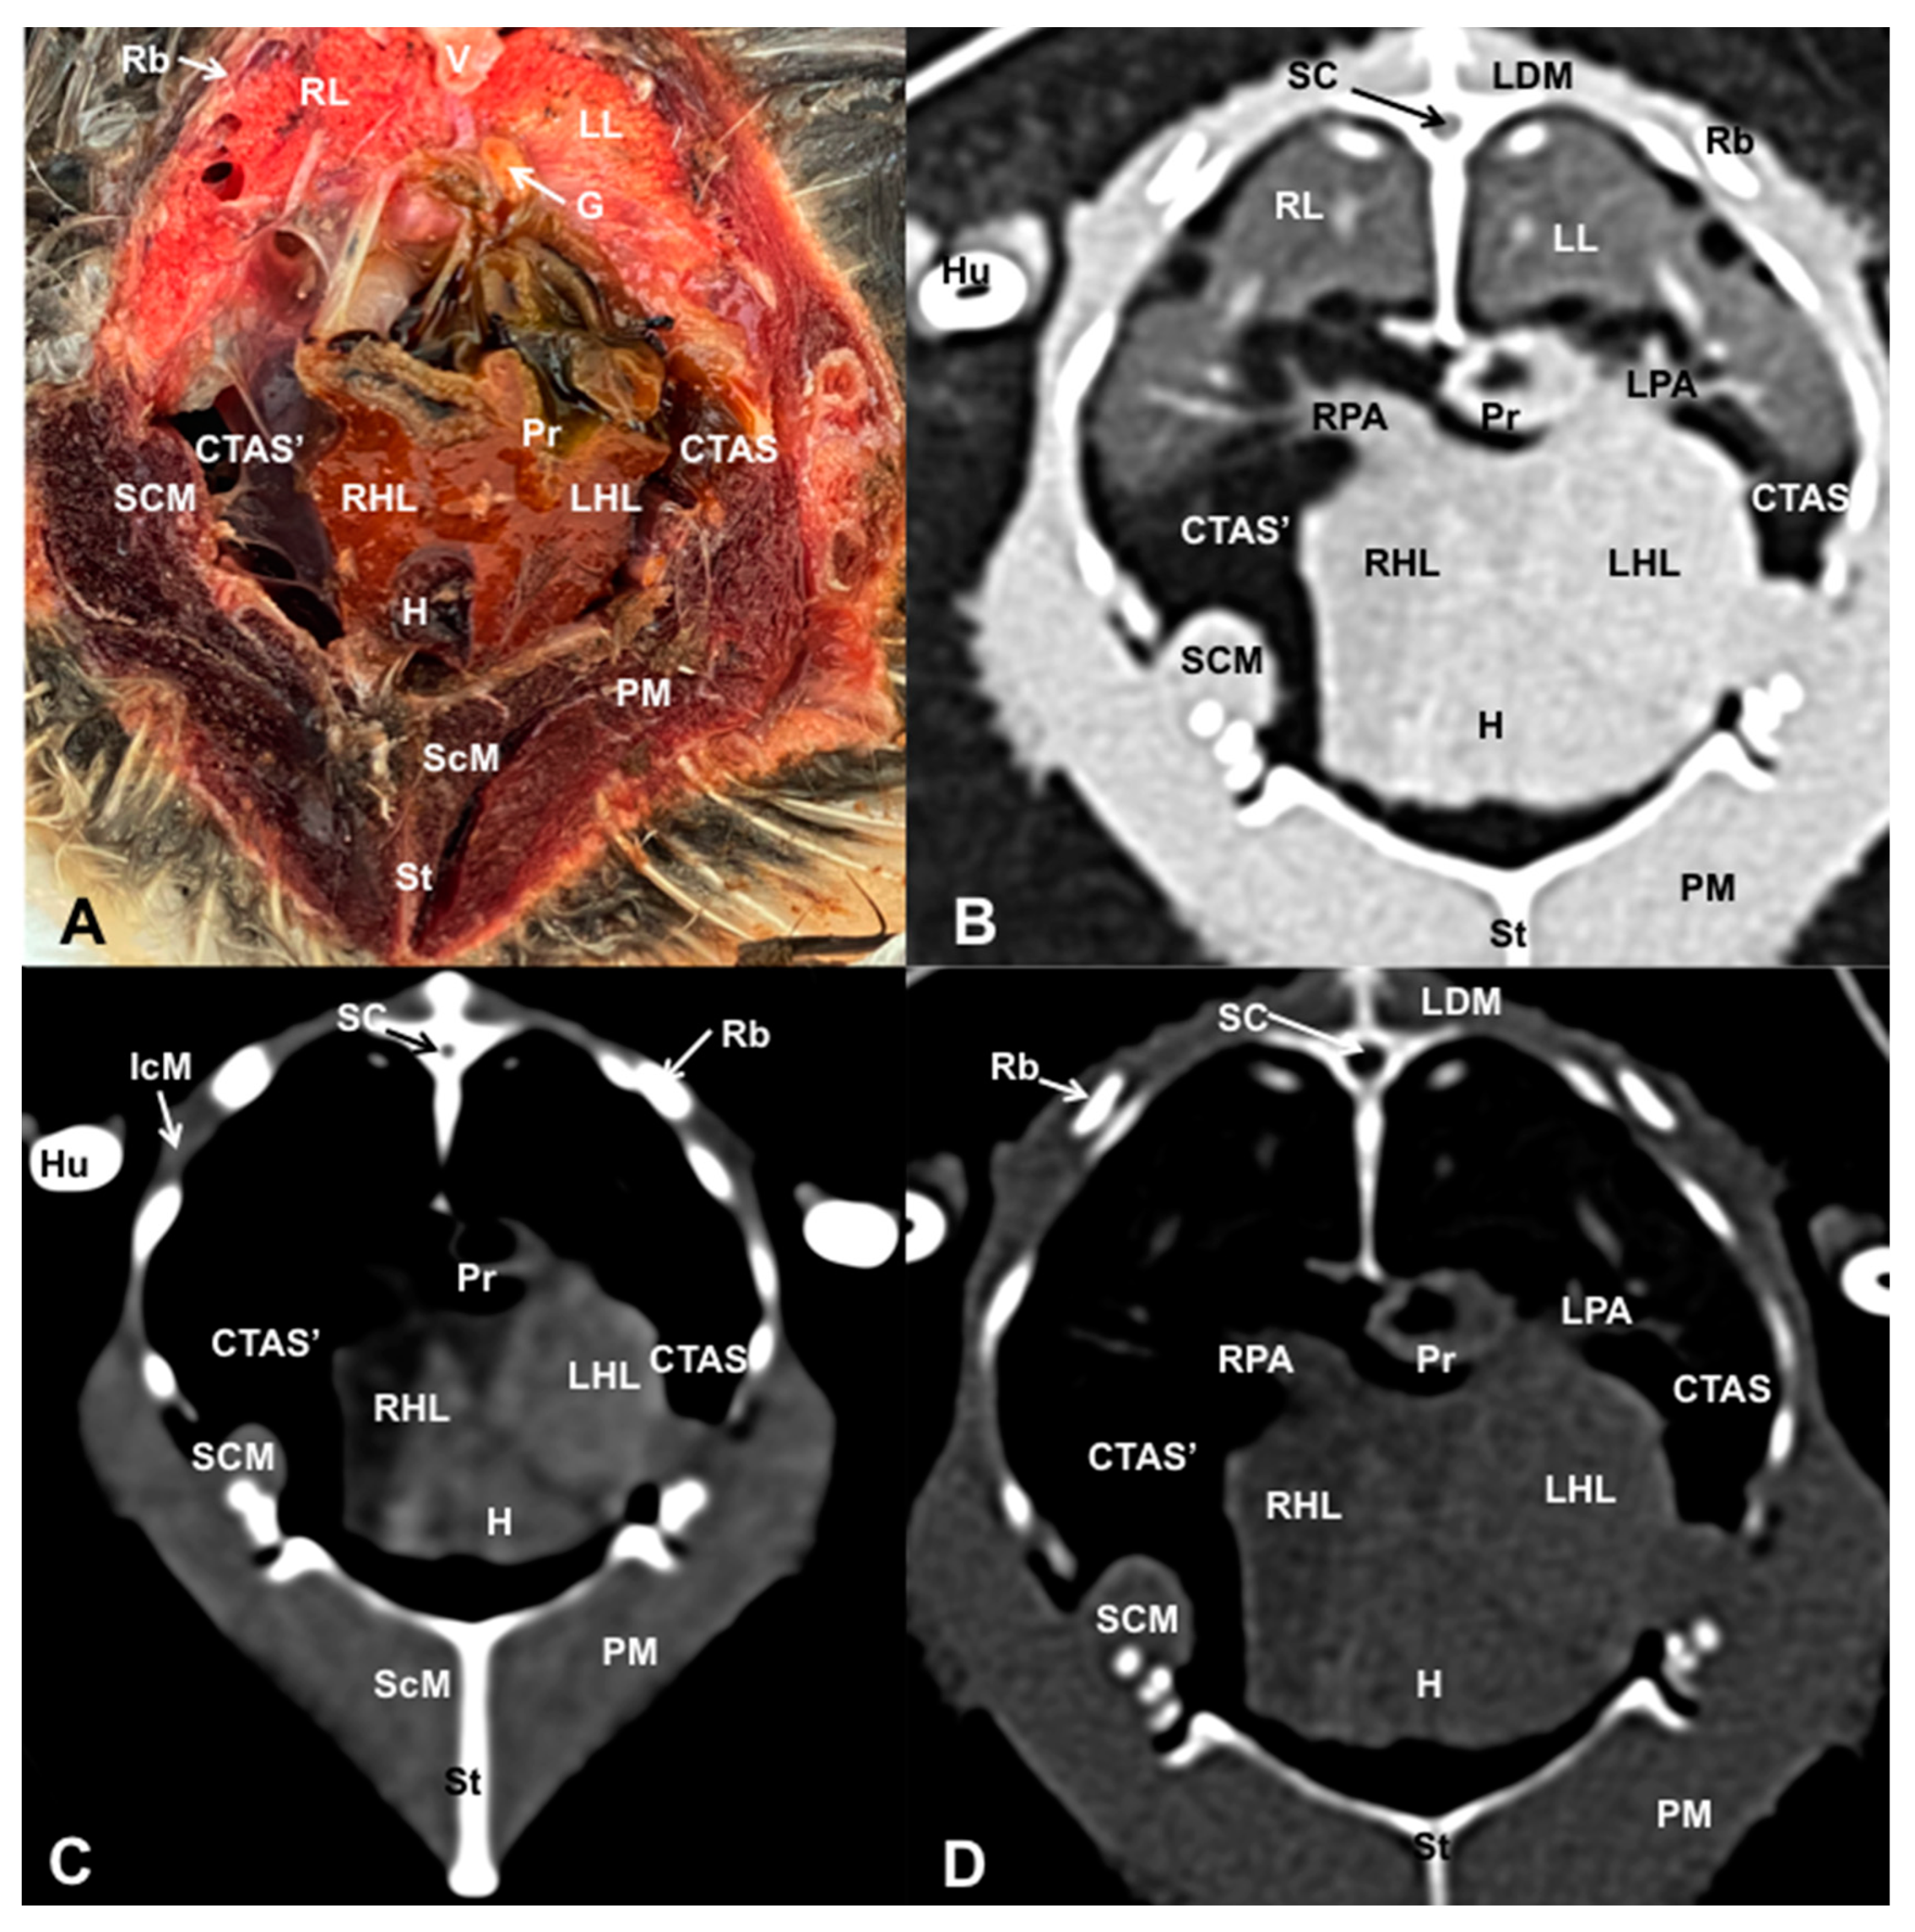

3.1. Anatomical Dissections and Cross-Sections

3.2. Computed Tomography Images